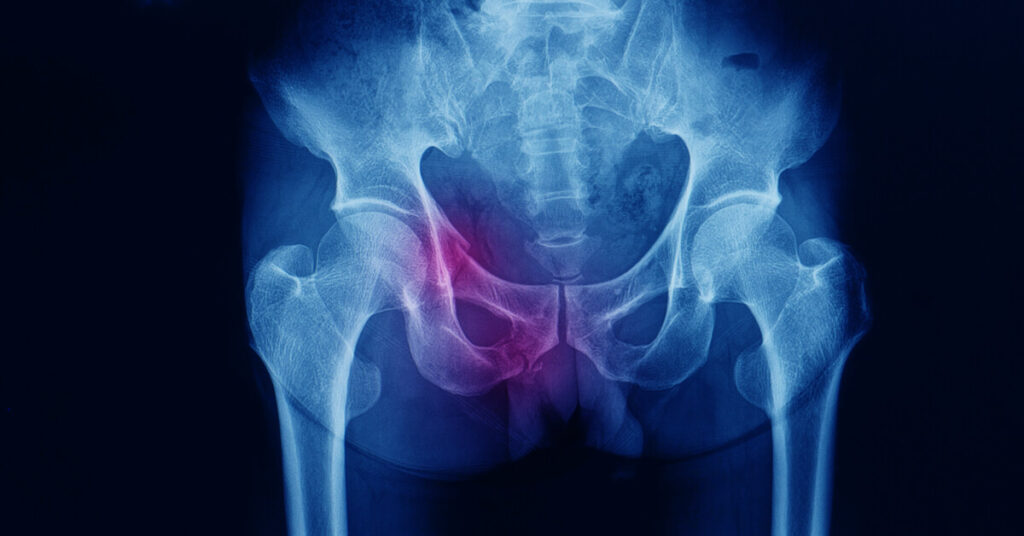

تكلفة عملية كسر الحوض، كسر الحوض من الإصابات التي تحدث بشكل شائع بين كبار السن والأشخاص التي تعاني من هشاشة العظام وعليه فإن المريض يبحث عن أفضل طبيب يمكن أن يساعده في حل مشكلته ولكي يتخلص من الألم الذي يعانيه، ونحن من خلال تلك الفقرات سوف نسلط الضوء على كسر الحوض وأسبابه وأعراضه وكيفية إجراء العملية والنتائج المترتبة عليها فكن معنا.

كما سبق وبينا لكم فإن كسر الحوض هو إصابة خطيرة تحدث عندما يتم كسر عظام الحوض، وهذا النوع من الإصابات غالباً ما يتطلب عناية طبية فورية والأعراض التي قد تظهر في حالة كسر الحوض والتي حددها الدكتور عمرو أمل أفضل دكتور عظام ومفاصل في مصر تشمل الآتي:

- يمكن أن يكون الألم شديدًا في منطقة الحوض أو الظهر السفلي، وقد يزيد الألم عند الحركة أو الضغط على المنطقة المصابة.

- قد تظهر منطقة الحوض تورمًا وكدمات بسبب الإصابة.

- قد يصعب على المصاب التحرك أو الوقوف بشكل طبيعي بسبب الألم والضرر في منطقة الحوض.